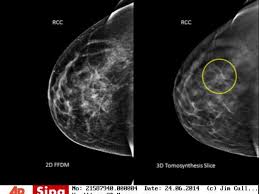

Cancer du sein : hausse inquiétante chez les jeunes femmes depuis trente ans